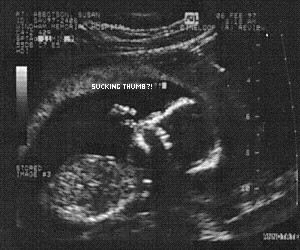

And take a peek at our newest member. A Humu in vitro! #1#2#3#4